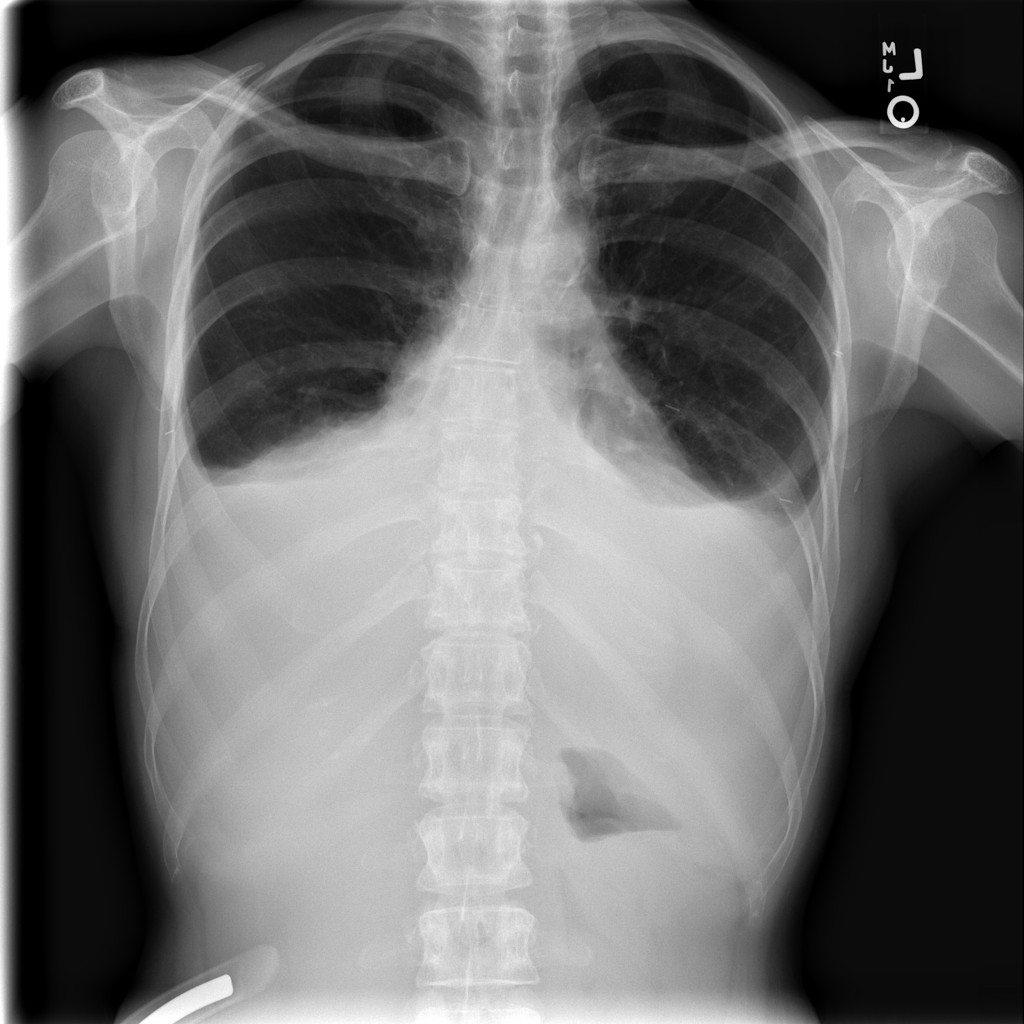

PAT-40F9 · IMG-004Effusion

PAT-40F9 · IMG-004

PA